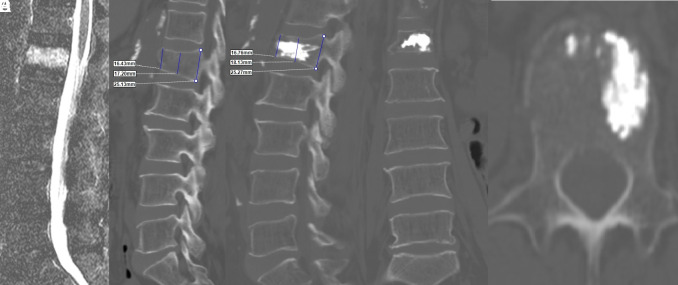

Methods: In this retrospective study, we reviewed data from 96 patients who underwent single-level unilateral kyphoplasty. The patients were categorized into 2 groups based on the cement volume injected: group 1 (cement volume "4 mL, minimum 3 mL; n=48) and group 2 (cement volume >4 mL, maximum 6 mL; n=48). The clinical outcomes, as assessed using the Oswestry Disability Index (ODI) and visual analog scale (VAS) scores, were evaluated preoperatively and then at the final follow-up 1 month postoperatively. The vertebral corpus height at the fracture level was measured at the anterior, middle, and posterior regions through sagittal computed tomography scanning.

Results: The mean age of the patients was 64.2 years in group 1 and 63.8 years in group 2. In group 1, the mean anterior vertebral height increased from 19.0 ± 3.3 mm preoperatively to 19.9 ± 3.2 mm postoperatively, whereas in group 2, it increased from 17.9 ± 3.8 mm to 19.6 ± 3.7 mm, respectively. The middle vertebral heights were 15.4 ± 2.5 mm preoperatively and 16.9 ± 2.8 mm postoperatively in group 1 and 16.0 ± 3.6 mm and 17.5 ± 3.2 mm, respectively, in group 2. Both groups exhibited significant improvements in ODI and VAS scores, with no significant di#erence between the groups. A statistically significant increase was recorded within each group for the anterior, middle, and posterior vertebral heights. However, a significantly greater increase was noted in the anterior height in group 2 compared to that in group 1 (P < .05).